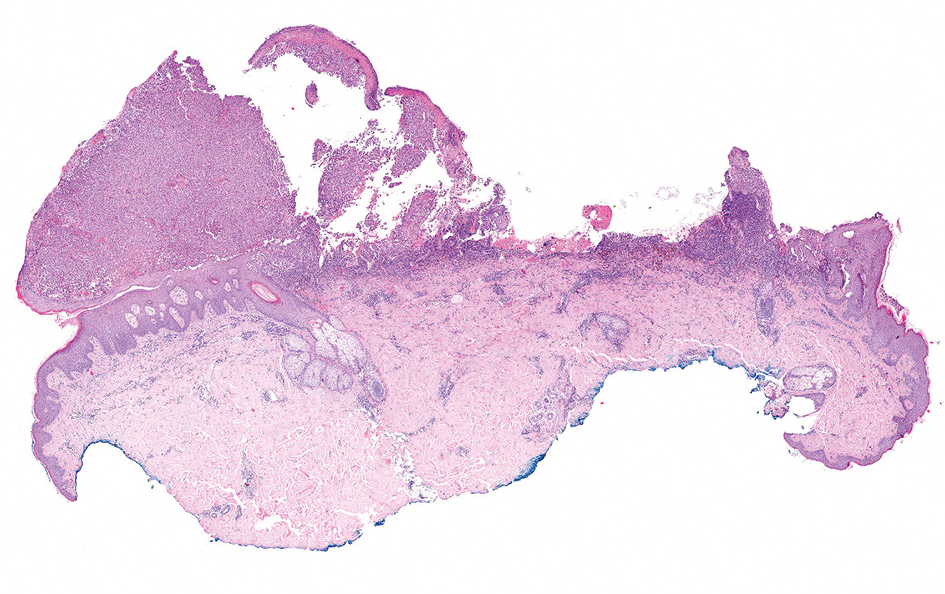

Figuur 2 | Excisiepreparaat melanoom in HE-kleuring (10 maal)

Excisiepreparaat melanoom in HE-kleuring (10 maal)

Patiënte B is een 23-jarige vrouw die in september haar huisarts bezoekt vanwege een veranderende, jeukende moedervlek op haar rechter schouder. De laesie bloedt en de huisarts vermoedt dat dit komt doordat ze eraan krabt en stelt haar gerust. In november ziet haar huisarts duidelijke veranderingen en verwijst haar alsnog naar de dermatoloog. Vanwege de jonge leeftijd van de patiënte denkt de huisarts niet aan een maligniteit en zet hij geen spoedverwijzing in gang. De patiënte krijgt voor januari een nieuwe afspraak. Ze besluit niet naar die afspraak te gaan vanwege de hoge kosten door het verplichte eigen risico en vraagt de huisarts om de excisie zelf te verrichten. Omdat deze geen noodzaak ziet tot nader histopathologisch onderzoek en dit bovendien extra kosten met zich mee zou brengen, besluit hij in overleg met de patiënte de moedervlek niet op te sturen. Tijdens de ingreep blijkt echter dat de plek gemakkelijk bloedt en daarom besluit de huisarts toch histopathologisch onderzoek te laten doen. Dat brengt een in de bodem niet radicaal verwijderd, superficieel spreidend melanoom met een breslowdikte van 2,5 mm met ulceratie aan het licht [figuur 2 en 3]. Na verwijzing volgen een re-excisie van het litteken met 2 cm marge met de sentinel node-procedure, en een aanvullende PET-CT-scan. De tumor blijkt volledig verwijderd, maar er is wel een macrometastase met een doorsnede van 6 mm in de sentinel node uit de rechter axilla. Er zijn geen aanwijzingen voor metastasen op afstand (classificatie pT3bN1aM0 Stadium IIIC). De patiënte krijgt een verwijzing naar een tertiair melanomencentrum voor eventuele aanvullende systemische therapie in trialverband.